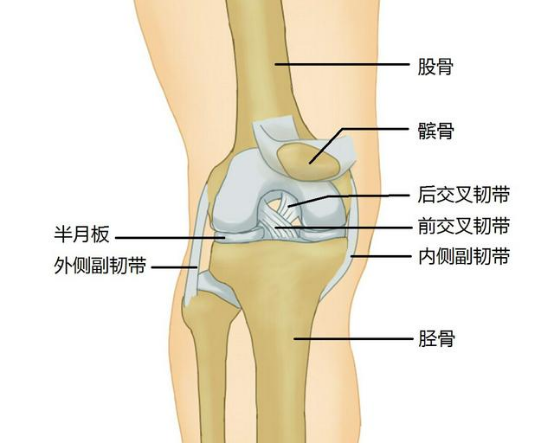

1.膝关节的组成

膝关节是人体最复杂的运动关节,其功能如同铰链。膝关节主要由股骨、胫骨和髌骨,以及其周围的关节囊、肌肉、肌腱、韧带包裹连接组成。这些连接结构给膝关节提供稳定性以及灵活的关节功能。